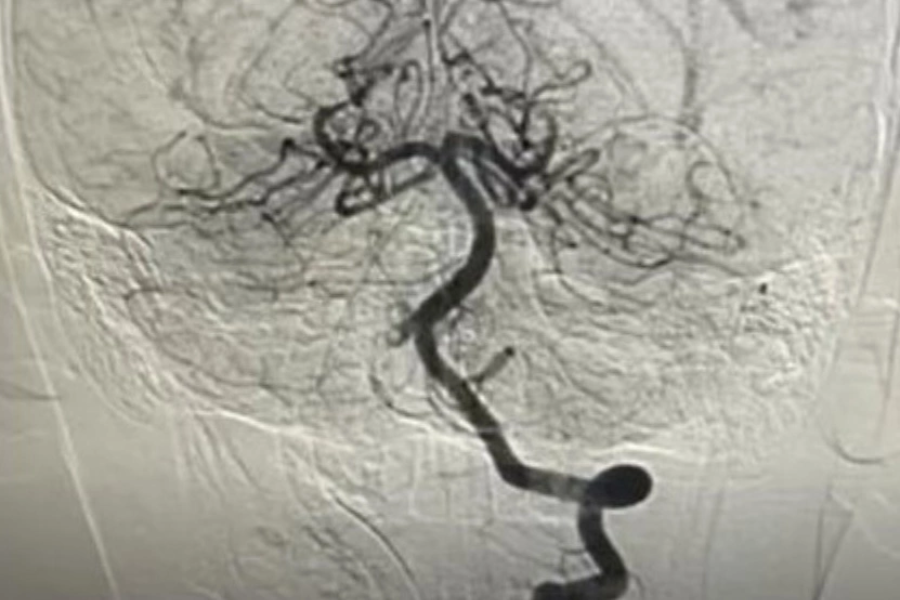

Một bé trai 10 tuổi sau khi tham gia hoạt động thể thao xuất hiện đau đầu dữ dội, nôn ói, rối loạn đi đứng và yếu dần nửa người trái. Bệnh viện Nhi đồng Thành phố cho biết MRI ghi nhận nhồi máu não cấp, kèm huyết khối gần như tắc hoàn toàn động mạch đốt sống phải. Trước đó không ghi nhận chấn thương hay va đập.

Bé được chụp mạch máu não và can thiệp nội mạch cấp cứu, tiêu sợi huyết tại chỗ kết hợp hút huyết khối, tái thông hoàn toàn mạch máu. Sau một tuần điều trị, bệnh nhi tỉnh táo, vận động phục hồi gần như bình thường và không ghi nhận di chứng thần kinh.

Bệnh viện cho biết nhồi máu não ở trẻ hiếm gặp, nguyên nhân chủ yếu liên quan các yếu tố bệnh lý dẫn đến hình thành huyết khối. Trường hợp này chưa xác định được yếu tố cụ thể, và vận động thể lực không phải nguyên nhân trực tiếp. Nếu không can thiệp kịp thời trong 4,5 - 6 giờ đầu (có thể mở rộng tối đa 24 giờ), nguy cơ tử vong hoặc di chứng nặng có thể tới 50%, nguy cơ tái phát khoảng 15 - 20%. Phụ huynh được khuyến nghị ghi nhớ quy tắc BE FAST để nhận diện sớm dấu hiệu đột quỵ ở trẻ.